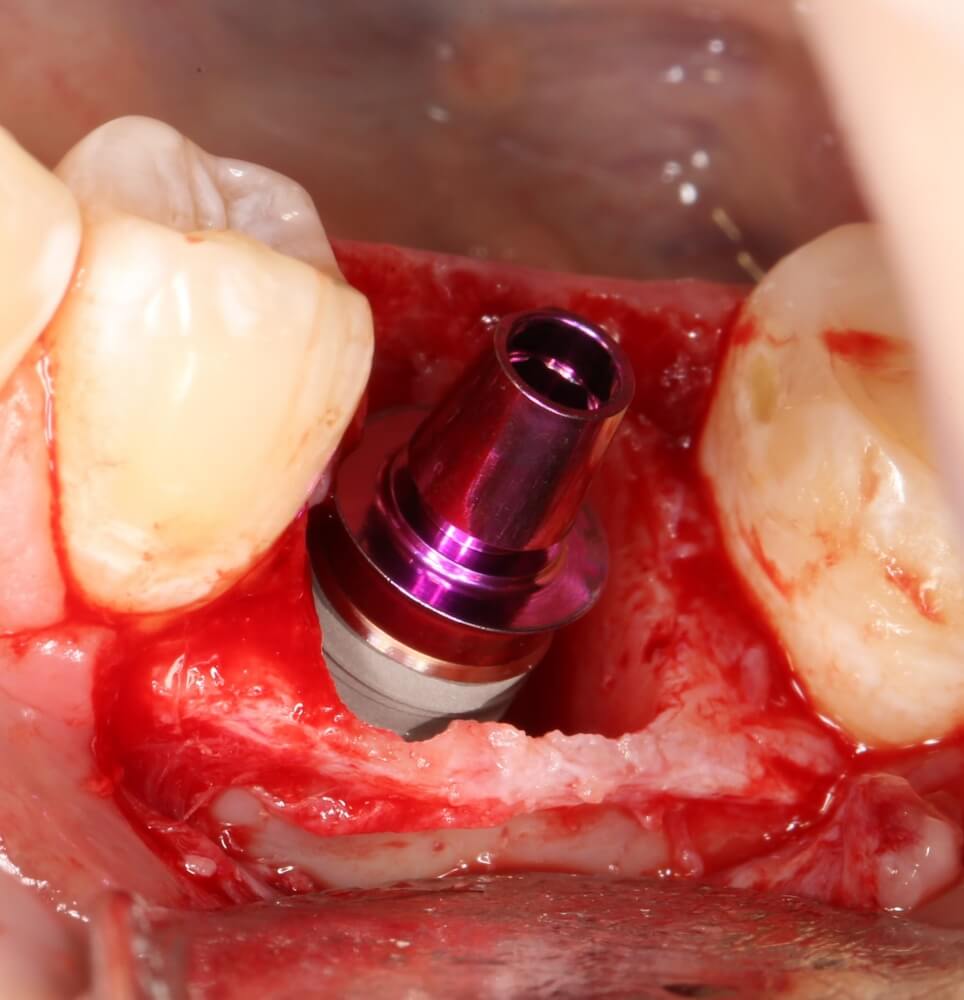

Прежде, чем приступить к аугментации (пластике) лунок зубов, мы подготовили лунки для имплантатов. В таких клинических случаях нет необходимости в использовании шаблона. Вместо этого, мы применяем общепринятые правила позиционирования и соблюдаем рекомендации производителя по хирургическому протоколу:

В процессе ирригации лунки промываются, что позволило нам еще раз подтвердить ранее сделанные выводы. С помощью аналогов имплантатов, входящих в хирургический набор Xive, мы проверили возможность стабилизации имплантатов в будущих лунках. Исходя из правил подбора и позиционирования имплантатов (я очень рекомендую почитать об этом здесь>>) мы остановились на Xive S диаметром 3,4 мм и длиной 13 мм.

Установка имплантатов

По ряду уже упомянутых выше причин, для решения этой клинической задачи мы выбрали имплантаты Xive. Лунки для них мы уже приготовили. возможную первичную стабильность оценили. Имплантаты мы установили с усилием чуть больше 15-20 Нсм — такого крутящего момента более, чем достаточно, особенно если учесть, что временные коронки будут соединяться между собой.

Подробно о том, что такое крутящий момент и хирургический протокол можно прочитать здесь>> и тут>>, соответственно. Из-за использования специальных индивидуализируемых временных абатментов, имеющих только три положения, нам нужно позиционировать платформу имплантатов по граням. Это очень просто  — мы выводим вырез абатмента TempBase (он входит в комплект поставки) вестибулярно.